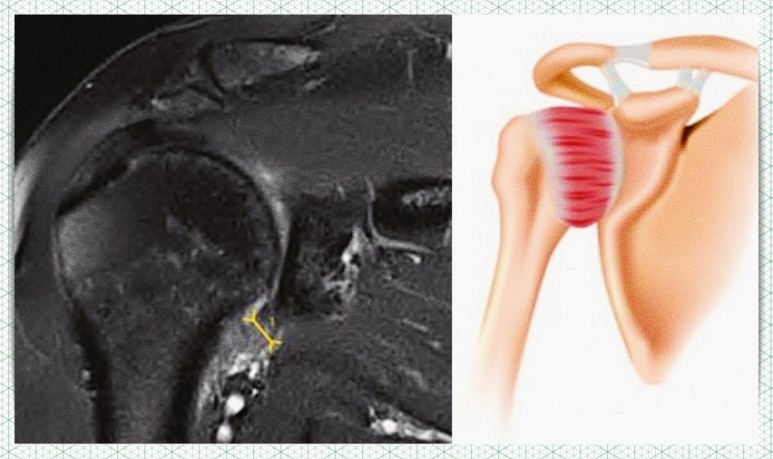

이 질환의 명칭은 ‘동결견’ 또는 ‘유착성 관절낭염’입니다. 그러나 대다수는 아마 오십견인 것으로 알고 있는 질환이라고 생각합니다. 그 이유는 50대 전후에 발생하는 경우가 많다고 알려져 있기 때문입니다. 물론 그런 시대도 있겠지만, 최근에는 젊은 환자도 증가하고 있는 것을 알고 계십니까?

물론 방금 든 어깨 통증이 모두 이 질환이라는 것은 아닙니다. 그 외에도 어깨충돌증후군, 회전근개파열, 탈구, 석회화건염, 관절과순파열, 견관절염 등의 문제가 발생할 수 있습니다.